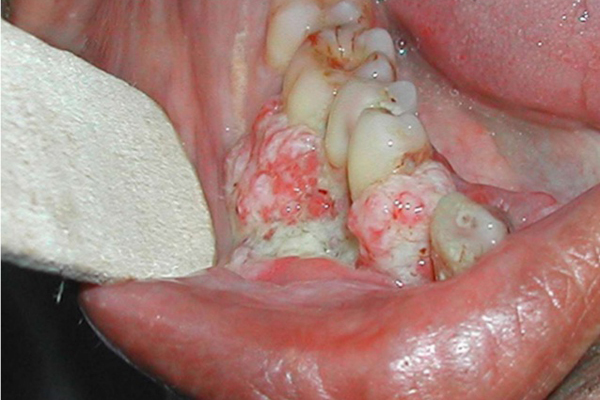

06/03/2019 22:50Tưởng bị nhiệt miệng, người đàn ông Hà Nội phải cắt 1 góc má vì ung thư

BSCK I Nguyễn Thanh Thái, Trưởng khoa Phẫu thuật Tạo hình hàm mặt, BV Việt Nam - Cu Ba cho biết, khi đến viện, khối u ở má trái bệnh nhân đã to 3-4 cm.

Rất ít trường hợp ung thư khoang miệng được phát hiện ở giai đoạn đầu bởi người bệnh hay nhầm lẫn là mắc nhiệt miệng hoặc loét miệng. Do đó người dân cần tự thường xuyên kiểm tra răng miệng, khi thấy những dấu hiệu sau cần đến BV thăm khám:

- Loét miệng kéo dài: Nếu trong miệng có vết loét không đau, hơi cứng, cộm nhưng 2-3 tuần không khỏi.

- Xuất hiện màu lạ trong miệng: Có thể là các vệt, đốm có màu đỏ hồng, trắng đục ở vị trí lưỡi, môi, nướu răng, niêm mạc má.

- U cục trong miệng: Một số trường hợp không bị đổi màu trong khoang miệng, không có vết loét mà xuất hiện u cục. Người bệnh có thể dễ dàng phát hiện bằng mắt thường hoặc sờ tay.

- Chảy máu trong khoang miệng: Chảy máu có thể tự nhiên hoặc sau khi va chạm nhẹ, sau ăn hoặc sau khi đánh răng.